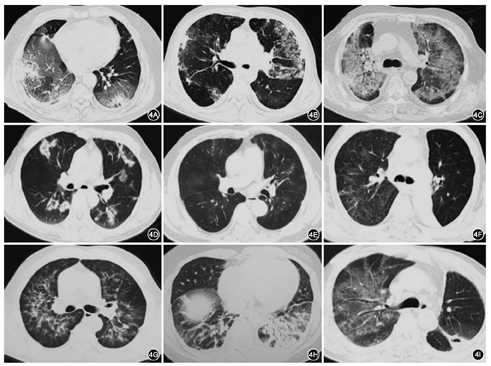

药物性肺间质疾病占ILD病因的2.5%~3%[13,14],免疫检查点抑制剂相关肺损伤发生率达5%~10%[15],靶向治疗相关肺损伤发生率在0.6%~3%[16,17]。尽管药物相关肺损伤属于罕见原因,但其影像学缺乏特异性(图4),随着疫情逐渐消退,肿瘤患者井喷式涌向医院,须与新冠肺炎相鉴别。

免疫检查点抑制剂引起肺损伤表现多样,中位发生时间在开始用药后2~3个月,但具体发生的时间范围可从用药后即刻至停药后。病程可为急性、亚急性,或隐匿起病。多数患者出现咳嗽、呼吸困难,1/3患者可合并发热,血象可正常或升高,血液中淋巴细胞计数可正常或降低,伴随炎性指标如C反应蛋白、ESR、IL-6等升高,临床表现与新冠肺炎难以鉴别。胸部影像学表现也缺乏特异性,可出现COP样,HP样、单纯的GGO、局部实变、网格状病变、小叶间隔增厚、牵张性支气管扩张等多种改变,少数快速进展的患者也可表现为ARDS样改变[18,19,20]。

肿瘤靶向药物有潜在的引起肺间质疾病的风险,表皮生长因子受体酪氨酸激酶抑制剂(EGFR-TKI)、间变淋巴瘤激酶(ALK)抑制剂,以及抗血管靶向药物索拉非尼、伊马替尼,抗CD-20单抗利妥昔单抗等均可引起肺损伤。靶向药物相关肺损伤多发生在用药后1个月内,为急性起病,临床上表现为咳嗽、呼吸困难,偶可合并发热、皮疹等全身症状,影像学可表现为双肺GGO、间质索条网格影、实变影或小叶间隔增厚等。在临床上经常需要与PJP、病毒性肺炎等感染性疾病相鉴别[21,22]。